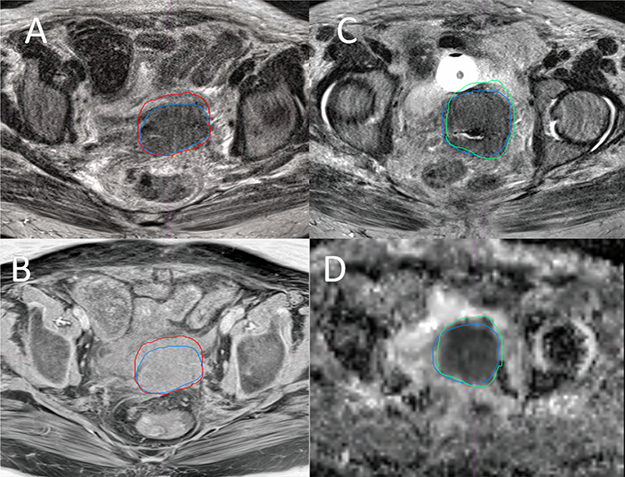

Figure 4A and 4B show the overlay of GTV-T1 and GTV-T2 for a representative case. As it is shown, GTV-T1 has a larger volume than GTV-T2, which is generally true for other cases. The difference is mainly due to the lower soft tissue contrast at the tumor boundary in T1 compared to T2. On the contrary, Figure 4C and 4D show that GTV-ADC is generally smaller than GTV-T2, however, encompassing suspicious regions that are sometimes not revealed by T2 because of different imaging mechanisms. The uncovered volume accounts for up to 16% of the GTV-T2. To resolve the issues with GTV-T2 and GTV-ADC, we propose to create a GTV based on the union of the GTV-T2 and GTV-ADC, referred to the MRI-based GTV (GTV-MRI).

Figure 4: Overlay of the GTVs from four MRI sequences of a Stage IVA cervical tumor. Overlay of GTV-T2 (blue) and GTV-T1 (red) on a T2 (A) and a T1 (B) slices, and overlay of GTV-T2 (blue) and GTV-ADC (green) on a T2 (C) and an ADC (D) slices, where GTV-T2 = 98.4 cm3, GTV-T1= 110.2 cm3, and GTV-ADC = 90.8 cm3.

In this study, differences were shown in the GTVs defined with different MRI sequences. In general, GTV-ADC is the smallest and GTV-T1 and GTV-T1 F+ are the largest, with GTV-T2 in between. The average ORs for GTV-T1, GTV-T1F+, and GTV-ADC relative to GTV-T2 were 86.3%, 81.6%, and 61.6% while the corresponding average RVRs were 113.8%, 112.3% and 77.2%, respectively. As shown in Figure 4A and 4B, GTV-T1 is generally larger than GTV-T2 mainly due to the lower soft tissue contrast at the tumor boundary in T1 images than T2 images. It is seen that the tumor border is clear, shown as the blue contour on T2 (Figure 4A), but not on T1 (Figure 4B)) (stage IVA, GTV-T2 98.4 cc, GTV-T1 110.2 cc). The front border of the GTV-T1 encloses a part of normal tissue (the small bowel wall). In contrast, as shown in Figure 4C and 4D, GTV-ADC was generally smaller than GTV-T2 and encompassed suspicious regions that are sometimes not indicated by T2 because of different imaging mechanisms. The uncovered volume accounts for up to 16% of the GTV-T2. Due to these reasons, the GTV-MRI, generated from the union of the GTV-T2 and GTV-ADC, may be more appropriate than individual GTV-T2 or GTV-ADC.